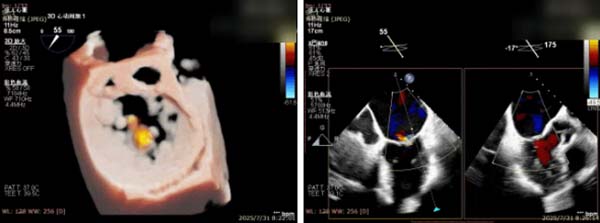

术前完善经食管超声评估,提示该患者双房大,二尖瓣重度反流4+伴后叶脱垂、后叶部分腱索断裂。根据评估结果,心脏大血管外科王安彪主任团队制定了周密的手术方案:植入一枚夹合器,钳夹P1区反流最大处,尽可能夹持全部后叶脱垂瓣叶组织,后续根据术中实时残余分流和跨瓣压差等指标,并依据实时超声监测调整治疗策略。

三维评估;二尖瓣P1脱垂偏心性返流

术前影像